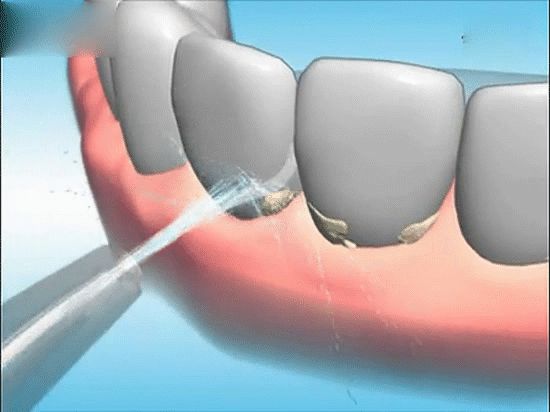

牙龈萎缩如果是病理性的则要通过正规的牙科医院来诊治,要积极的治疗牙周炎、牙龈炎,定期清理牙结石。对于使用假牙的人,如果假牙不适合,要提早的修整,定期的进行牙齿的保健。